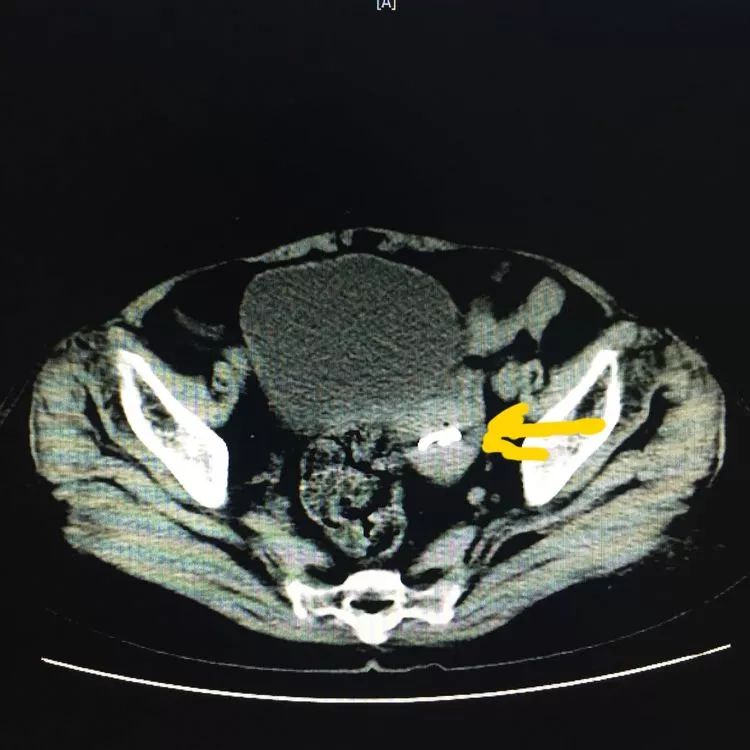

下面图中黄色箭头所指均为节育环的位置

近日,我院妇科接诊了一例困难型取环患者。患者蔚女士,年龄65岁,带环40余年,绝经期20年,近4年来无诱因出现下腹部胀痛,时轻时重,2年前曾在私人诊所取环,结果取出失败。现为求取环,患者及家属经过谨慎考虑,来我院。入院后妇科彩超提示:子宫萎缩,宫腔可见“O”形环回声,位置正常。马辉平主任考虑到患者绝经20年,子宫萎缩,曾经有过取环失败史,入院后经过各项详细检查排除,排除手术禁忌证,马辉平主任准备为其行宫腔镜下取环术,令人惊讶的是宫腔镜下居然没有见到节育环,却发现了个一个3✖️2.5厘米粘膜下肌瘤,蒂部来源于子宫前壁。马主任考虑节育器移位了,到底移位到了哪里呢?子宫肌层、盆腔、腹腔、膀胱等,这些部位的可能性都很大。为了进一步明确节育环移位的部位,又进行了透视及CT检查,均显示节育环在子宫内。